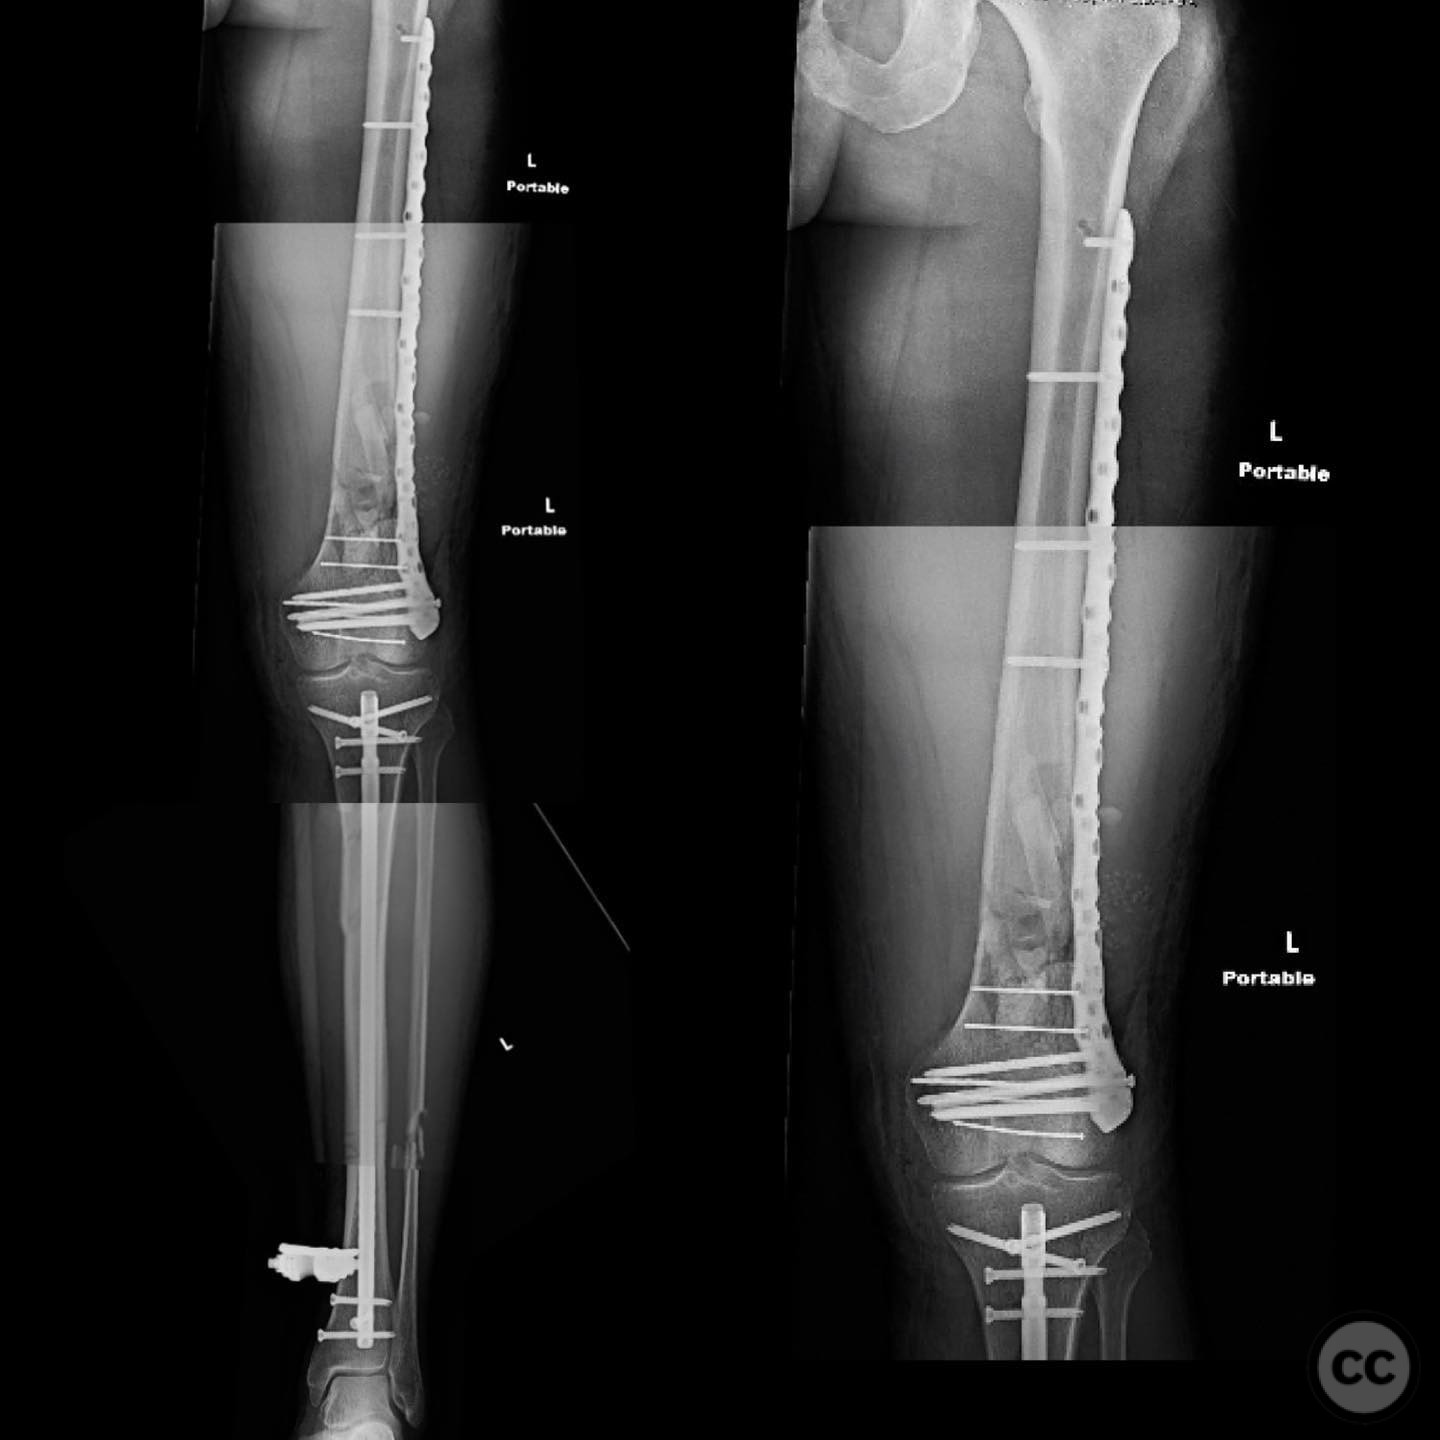

Patient positioning:  Supine positioning on a radiolucent table to facilitate fluoroscopic imaging. The affected limb was prepared for access to both the femur and tibia.

Anatomical surgical approach:  For the tibia, a longitudinal incision was made to access the proximal tibial start site for intramedullary nailing. Percutaneous clamps were utilized for reduction, supplemented by blocking screws as needed. For the distal femur, an external fixator was applied initially, followed by an in situ lateral approach for plating after reduction was achieved.

Operative remarks:

The tibial nailing required precise identification of the start site under fluoroscopic guidance, with percutaneous clamps aiding in reduction. Blocking screws were considered but not necessary due to successful reduction with clamps alone. The distal femur presented challenges in achieving coronal and sagittal alignment, necessitating reliance on the external fixator for reduction before proceeding with plating.

Postoperative protocol:   Postoperative rehabilitation included early mobilization with weight-bearing as tolerated on the tibia, while the femur required protection until definitive fixation was achieved. Progressive weight-bearing was introduced following femoral plating.

Orthopaedic implants used:   Intramedullary nail for tibia, external fixator for initial femoral stabilization, and locking plate for definitive femoral fixation.